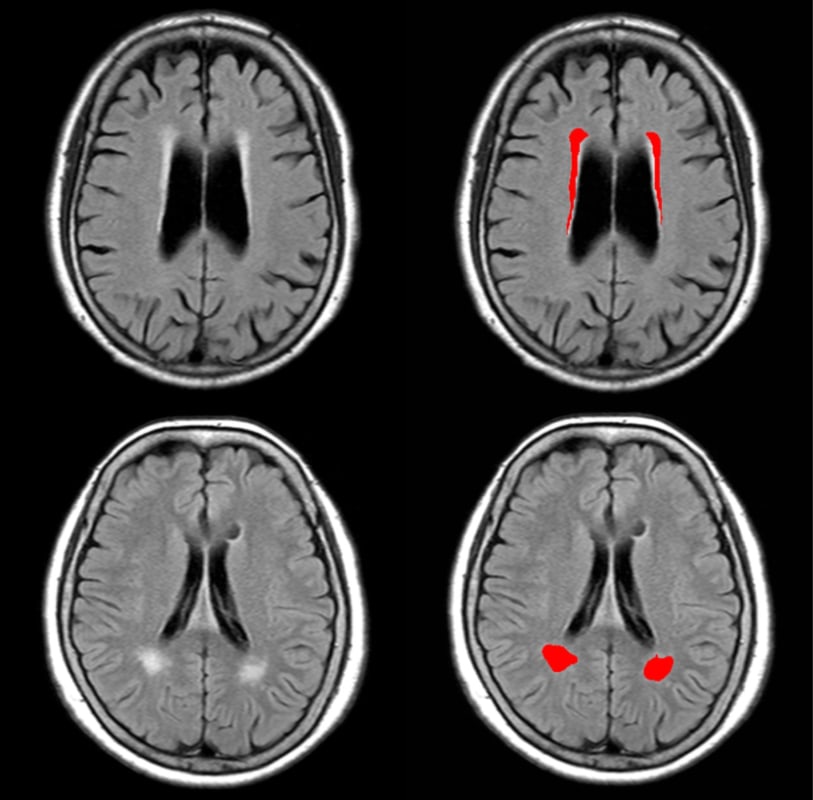

効率的な診断を期待できる

自動計測アルゴリズム

脳MRI画像から白質高信号領域・Evans index・Callosal angleを自動計測することで、白質等の評価における医師によるばらつきをなくします。